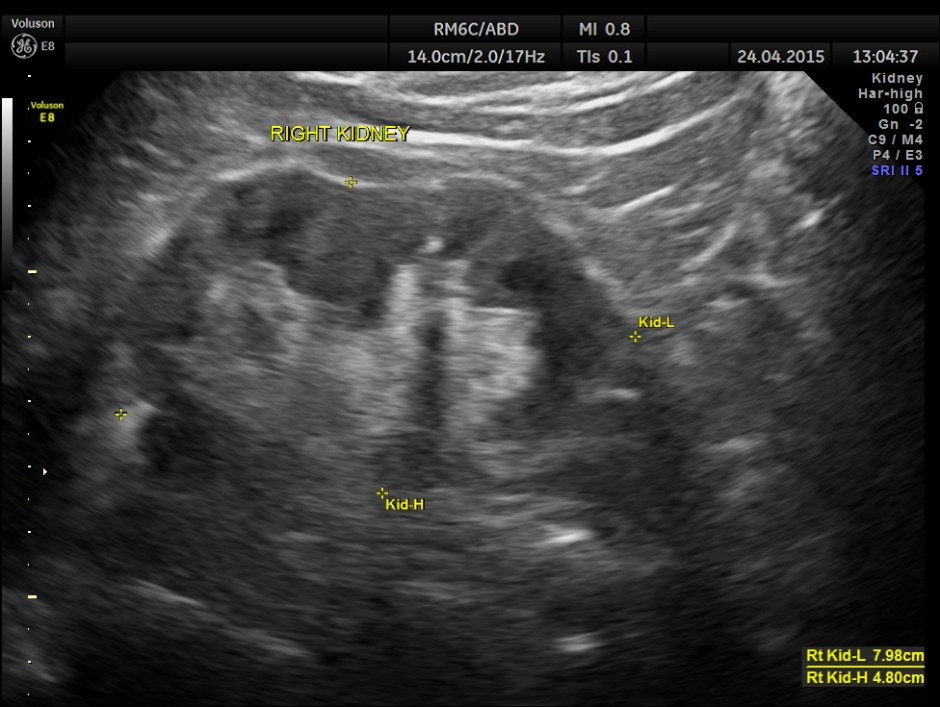

His ultrasound at present showed :

The kidneys show mild pelvi calyceal dilatation.